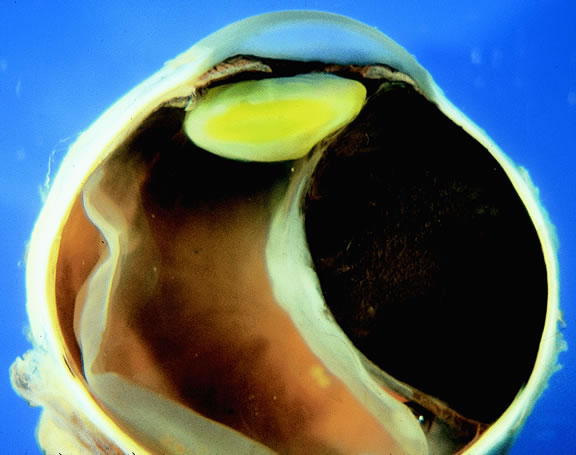

Gross Pathology

Choroidal melanomas initially arise in the stroma of the choroid. In early cases, the profile of the sectioned tumor is oval or almond-shaped, and its tissue usually appears relatively cohesive after fixation (Fig. 24). Although some tumors diffusely infiltrate the uvea, most uveal melanomas are relatively well-circumscribed tumors with distinct margins. In many cases the growing melanoma perforates Bruch's membrane and enters the subretinal space where its apex typically assumes a spherical shape that often is likened to a mushroom or collar button (see Figs. 19 to 22.). Dilated vessels often are found in the mushrooming head of the tumor because the ends of Bruch's membrane exert a compressive cinch-like effect on the waist of the tumor (see Fig. 22). Rupture of Bruch's membrane was present in 87.7% of 1527 large- or medium-sized melanomas examined in the COMS.84 Retinal invasion was present in nearly half (49.1%), and tumor cells were found in the vitreous body in one fourth.

Fig. 24. Cut surface of heavily pigmented choroidal melanoma is almond-shaped. Bruch's membrane is intact.